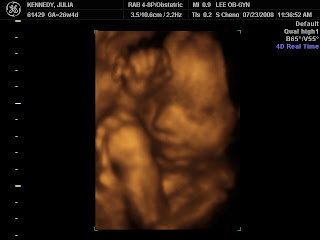

4D Ultrasound Today

Sophia Mae Kennedy under the camera.

I was not up for doing this...never really could "see" what

I was suppose to be seeing in ultrasound.

Steve said Monday...let's do it.

Ok, today it was pretty cool to get to see her in action.

I liked it when the lady just let her move around.

I was able to visualize the movements that have been going on.

I now know the difference when she is kicking and punching.

We also got to see a yawn.

hand above head

She really didn't want her picture taken today.

Kept holding hand up...

camera shy like her Daddy.